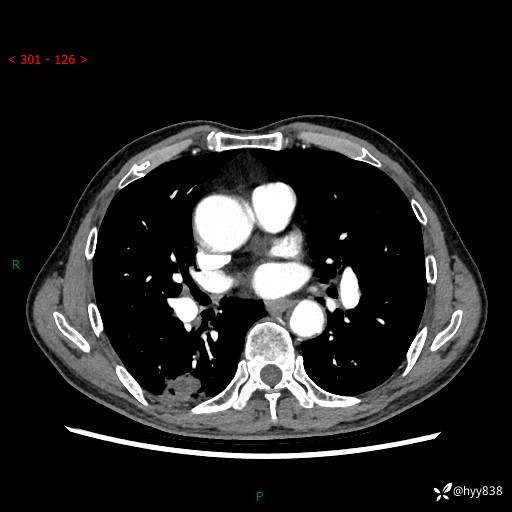

辅助检查:CT

胸部CT平扫

增强